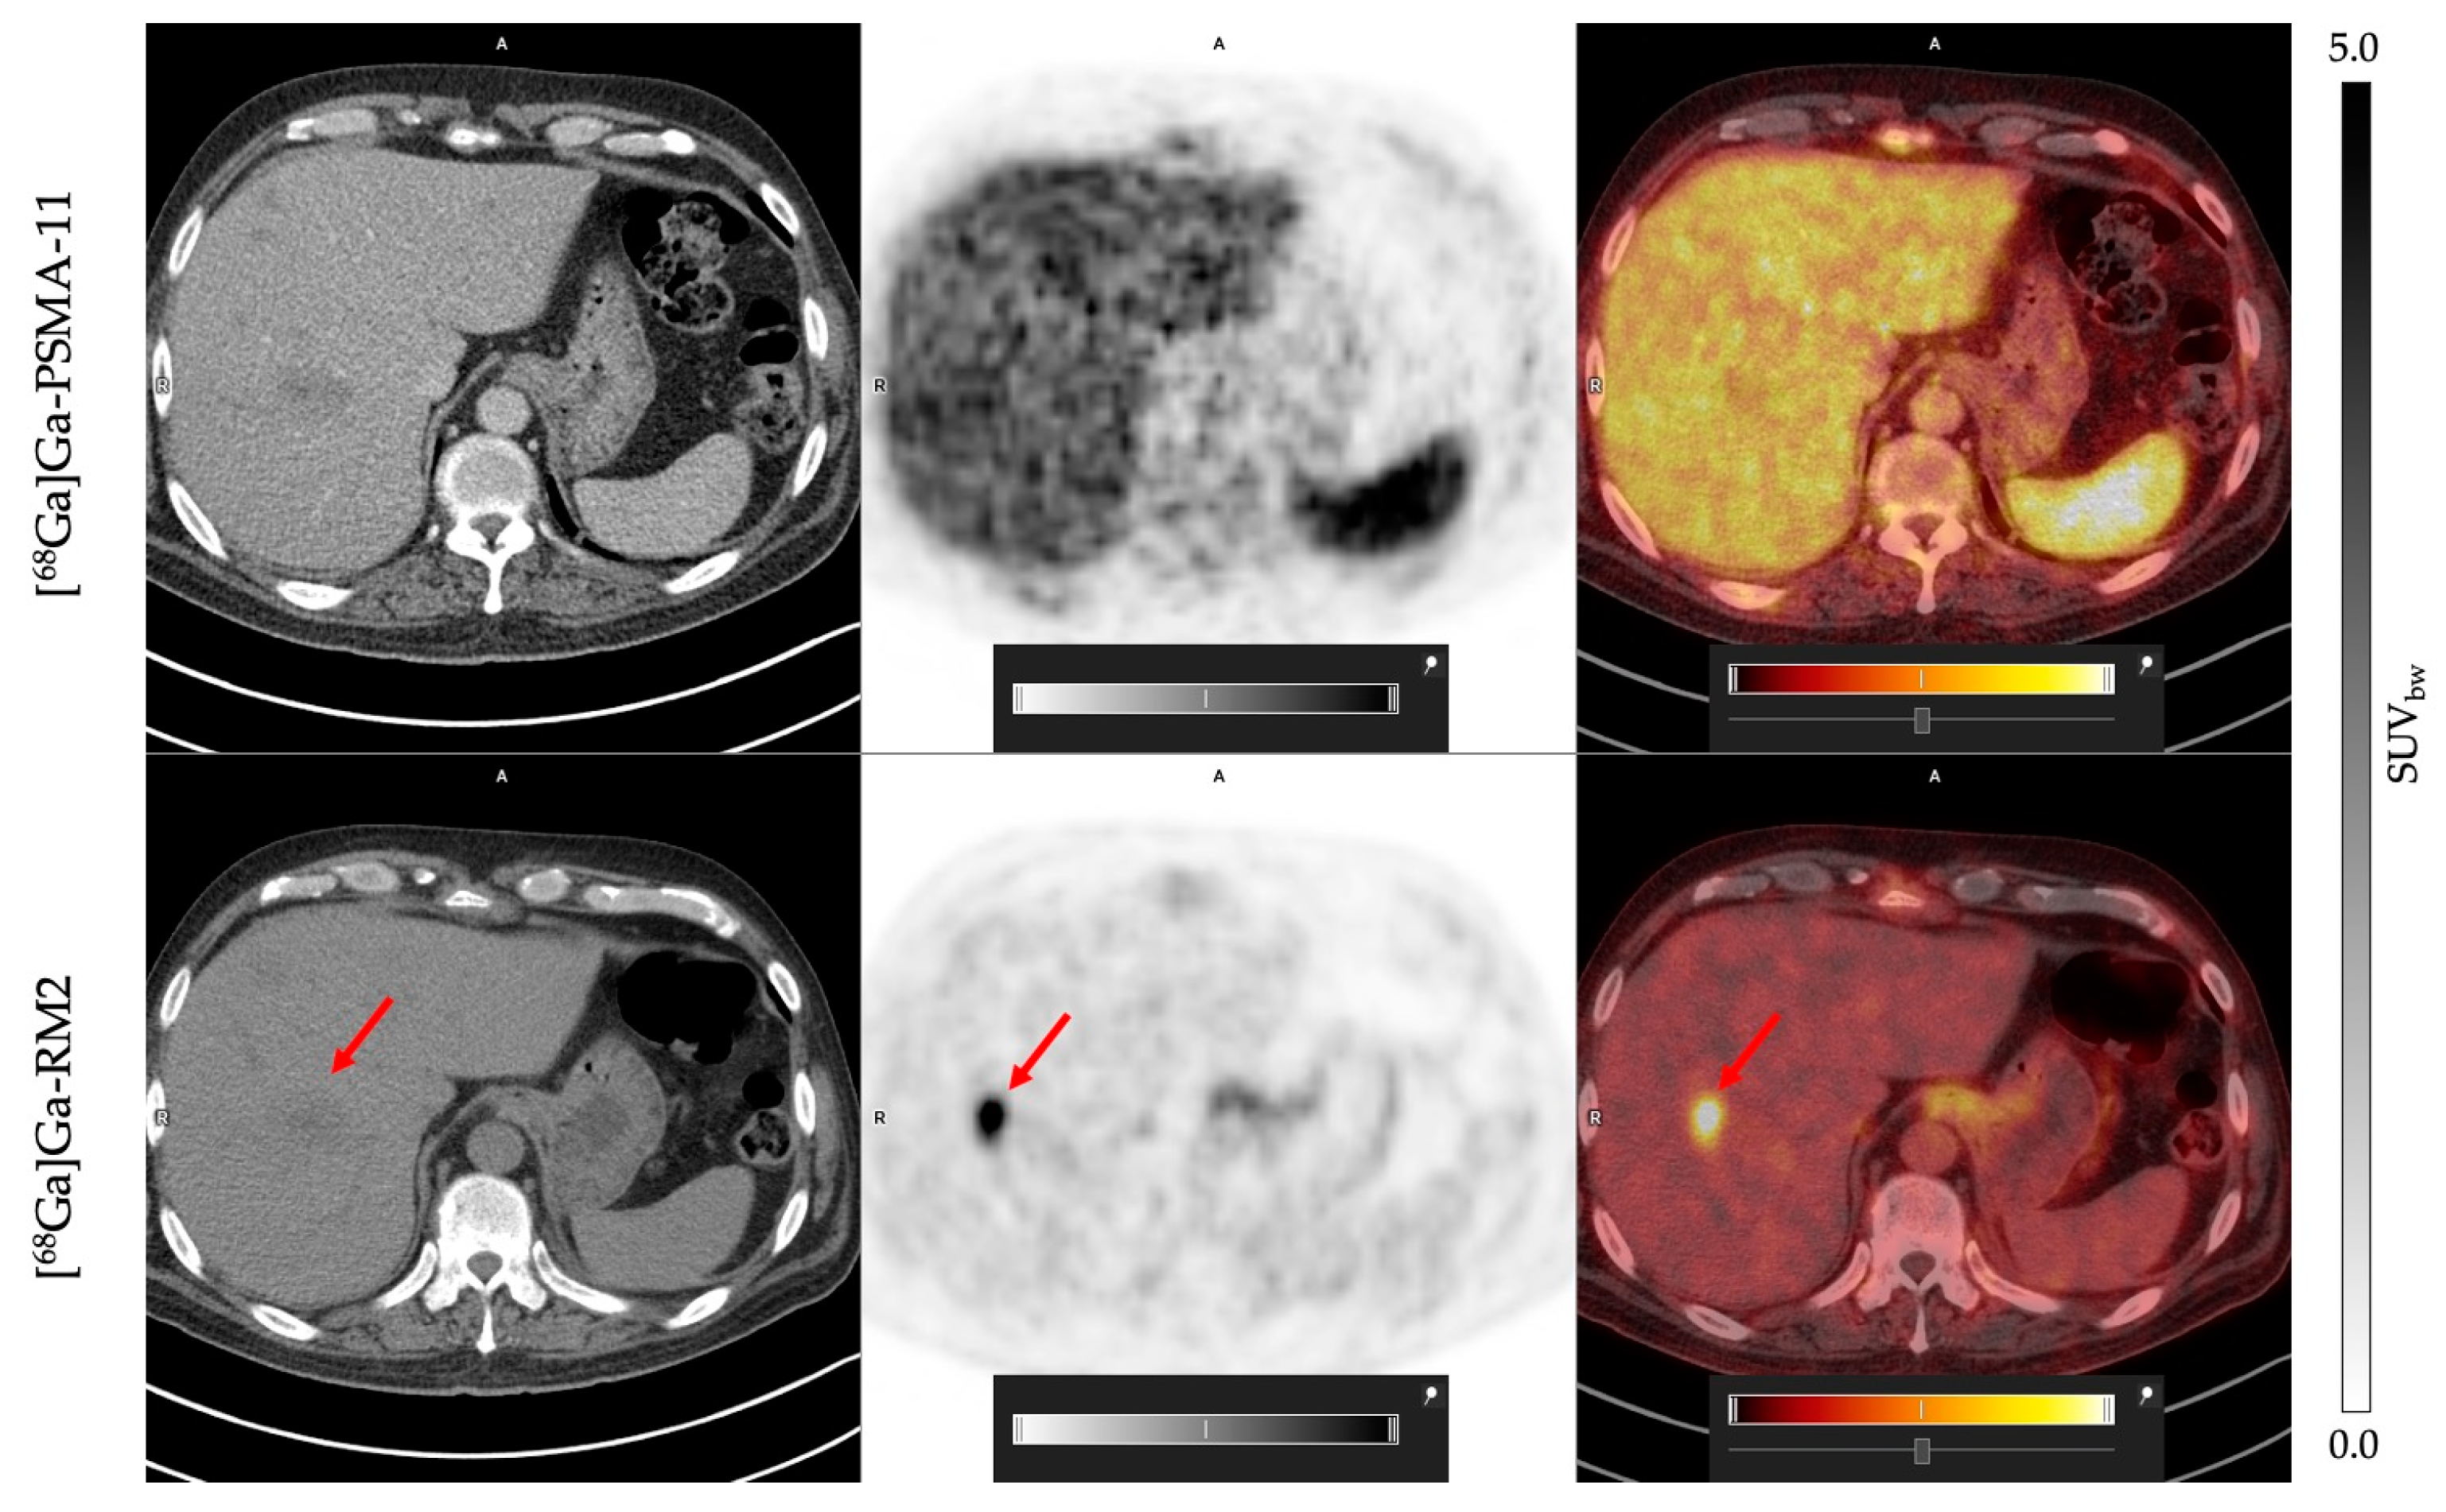

3.2. Uptake Comparison between [68Ga]Ga-PSMA-11 and [68Ga]Ga-RM2